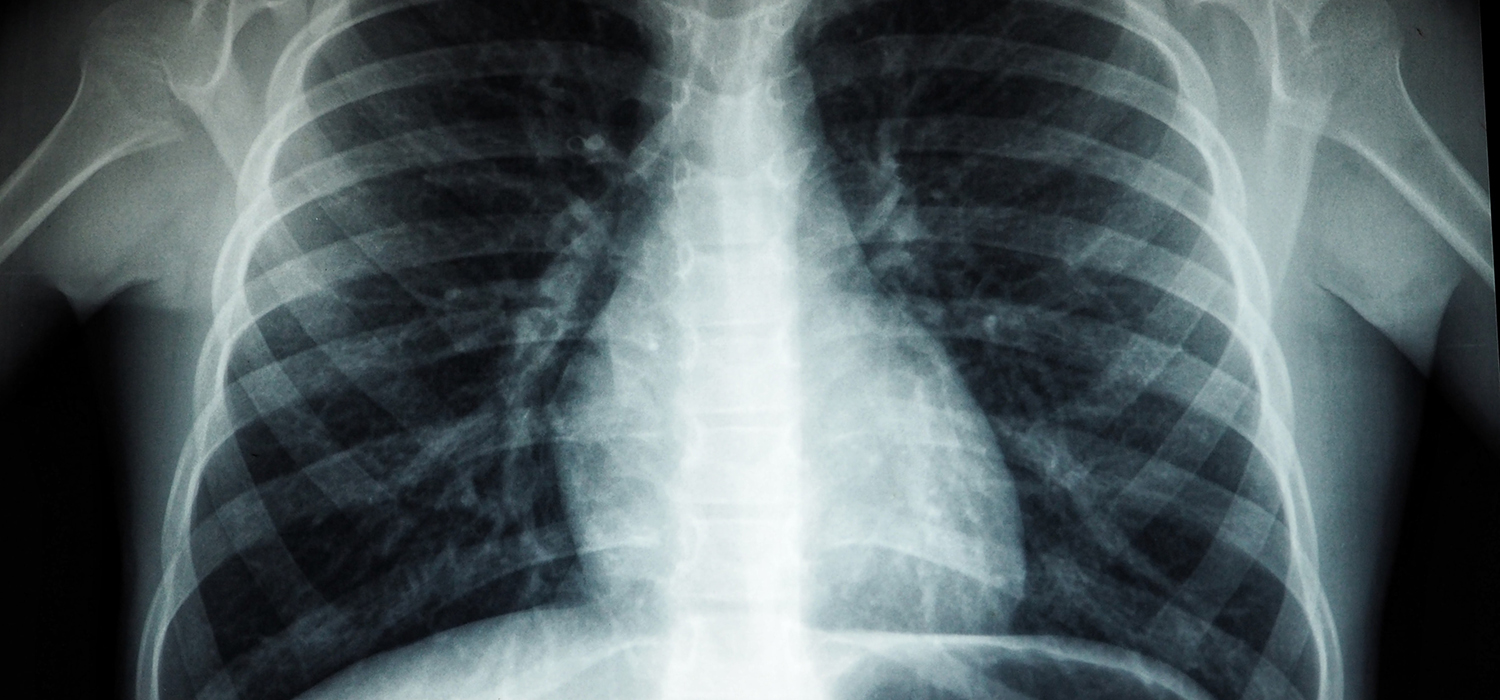

X-ray diagnostics have long been a cornerstone in medical imaging, enabling the...

In the field of medical diagnostics, X-ray machines have played a pivotal role in the early...

Imaging modalities, such as X-rays and CT scans, are commonly used in medical diagnosis and treatment. These...